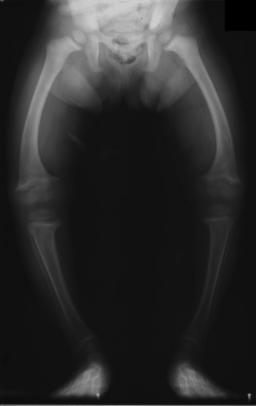

| تصوير بالأشعة لمريض بالرخد في الثانية من عمره، with a marked genu varum (bowing of the femurs) and decreased bone opacity, suggesting poor bone mineralization. | |

- الأطفال الصغار: تقوس الساقين (ركبة فحجاء)[4]

An X-ray or radiograph of an advanced sufferer from rickets tends to present in a classic way: bow legs (outward curve of long bone of the legs) and a deformed chest. Changes in the skull also occur causing a distinctive "square headed" appearance (Caput Quadratum). These deformities persist into adult life if not treated. Long-term consequences include permanent bends or disfiguration of the long bones, and a curved back.[5]

يصبح اتساع المشاش في المعصمين وعنقي القدم (النهايات السفلية للزند والكعبرة وعظم الفخذ والشظية)، واضحاً للعيان باستمرار الحدثية الرخدية، ويؤدي نقص تكلس العظام خاصة بعد بدء الطفل بالوقوف والمشي إلى تقوسات بالطرفين السفليين وتبدلات في الركبتين فيحدث الروح والفحج.

يبدأ الشفاء خلال أيام من استعمال كمية كافية من فيتامين د، ويتطور ببطء حتى يعود التعظم إلى حالة سوية، وفي حالات عديدة يختفي تشوه الأطراف والأضلاع واتساع المشاش والجمجمة بعد أشهر أو سنوات، حتى إن تقوس الساقين قد يزول خلال سنوات بدون جراحة. لكن قد تكون التبدلات دائمة في الحالات المتقدمة.